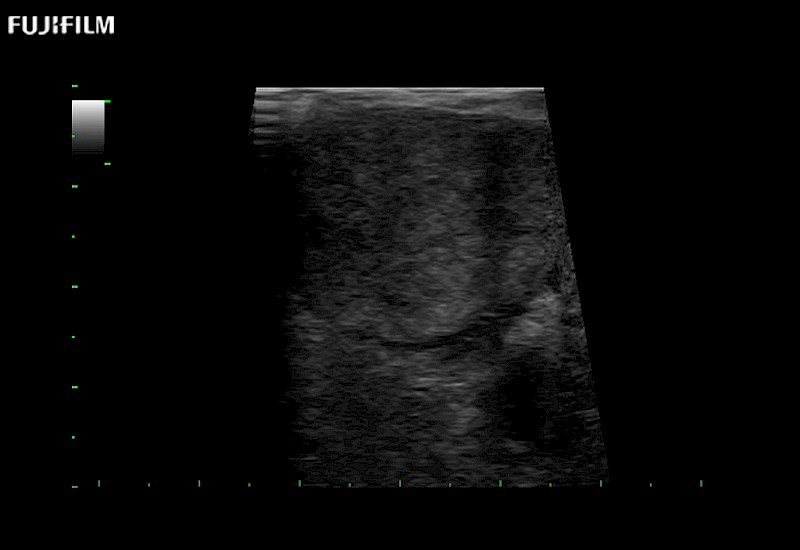

Curved array 4-way laparoscopic transducer for better visualization of targeted lesions.